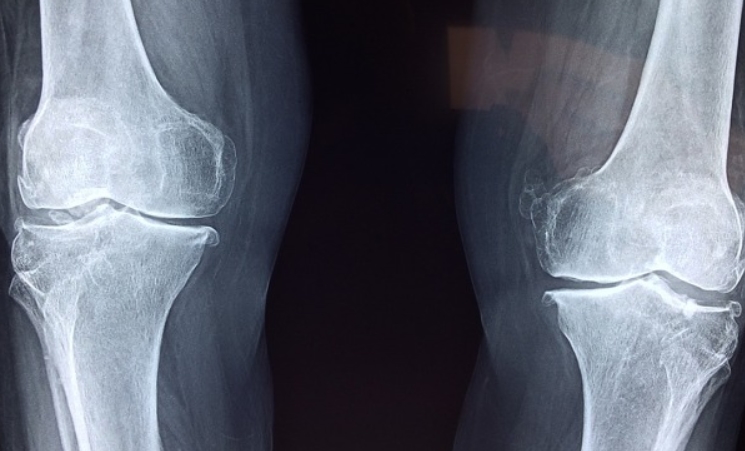

골다공증 수치

골다공증 여부를 확인하는 대표적인 방법은 골밀도 검사(BMD, Bone Mineral Density)입니다. 일반적으로 T-score를 기준으로 판단하는데, 이 수치는 건강한 젊은 성인의 평균 골밀도와 비교하여 나타냅니다.

- 정상: T-score -1.0 이상

- 골감소증: T-score -1.0 ~ -2.5

- 골다공증: T-score -2.5 이하

골밀도 검사 외에도 혈액 검사를 통해 칼슘, 비타민 D, 호르몬 수치를 확인할 수 있습니다. 폐경 후 여성의 경우 여성호르몬(에스트로겐) 감소가 골밀도 저하를 촉진하므로 정기적인 검진이 필요합니다.